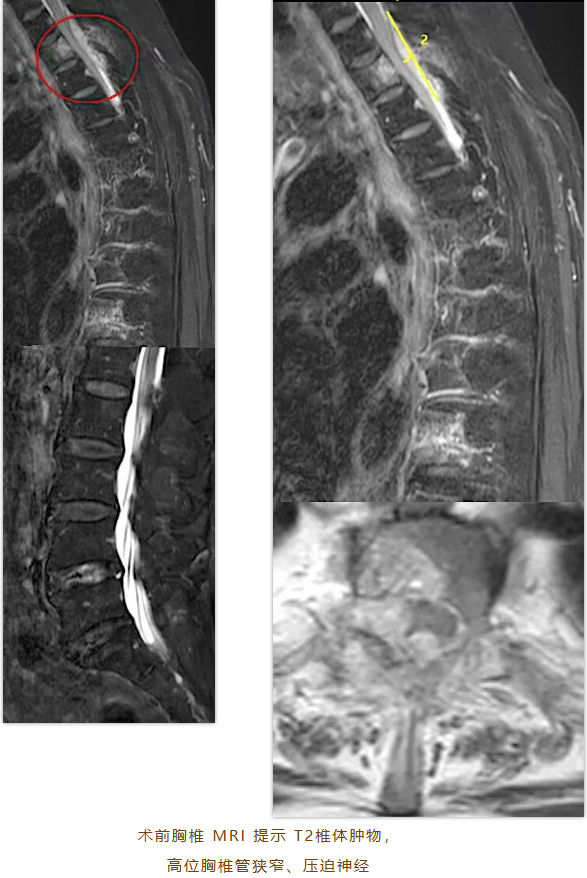

胸椎MRI检查结果令人揪心:劳阿姨高位胸椎椎管有个4.5cm*1.2cm的肿瘤,T2椎体及其右侧附件、棘突骨质破坏,邻近椎管后缘有异常信号,初步怀疑是侵袭性血管瘤或转移瘤;同时,T4、T5、T6、T8、T10椎体有血管瘤,T10椎体可能压缩性骨折。最终诊断为:高位胸椎椎管狭窄、T2椎体肿物、T10椎体血管瘤并椎体骨折、腰椎椎管狭窄症。

“胸椎区域靠近心肺等重要脏器,脊髓神经密集,高位胸椎手术空间小,稍有不慎就可能神经损伤致瘫痪。”陈教授介绍,患者高龄且合并多种病变,手术风险大。肿物性质不明,对手术剥离和止血技术要求极高。